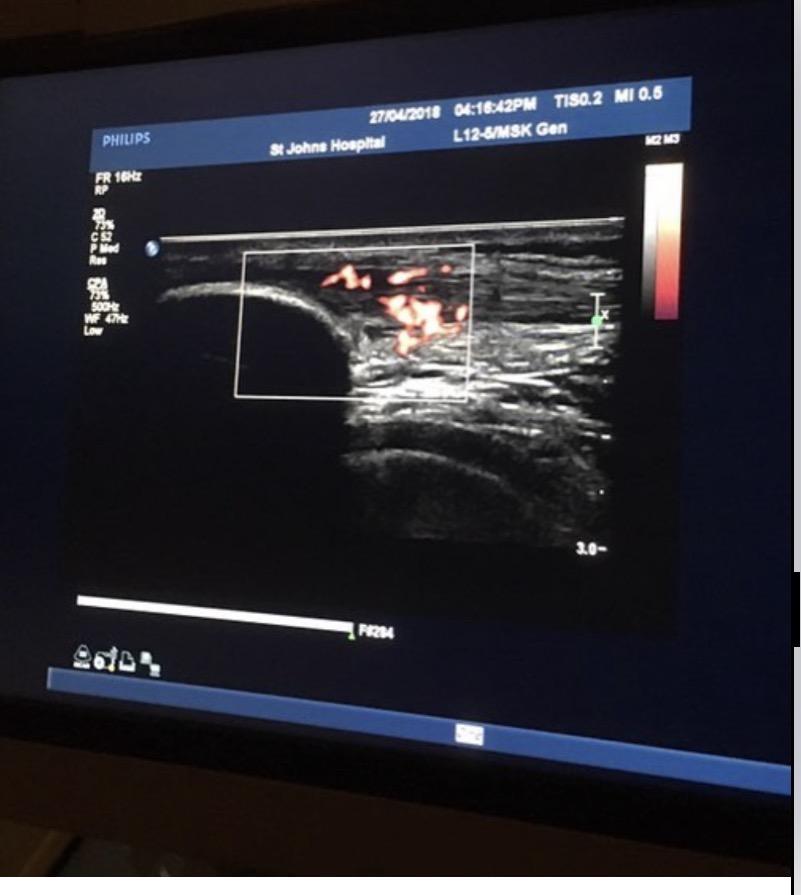

Ultrasound imaging demonstrated marked diffuse neovascularity within the patellar tendon — a finding commonly associated with long-standing, degenerative tendon pathology.At this stage, running simply wasn’t tolerated.

A follow-up ultrasound in February 2019 showed a slight reduction in Doppler signal (re-graded from very severe to severe), but clinically, nothing had changed.